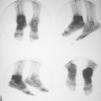

Fig. 5--Radiografía simple, anteroposterior y lateral, del tobillo derecho tras osteosíntesis. Caso clínico núm. 2.

Fig. 5.--Plain radiographs, anteroposterior and lateral, of the right ankle after osteosynthesis. Clinical case 2.

Fig. 6.--Radiografía simple, anteroposterior y lateral, de tobillo derecho tras la retirada del material de osteosíntesis. Se observan cambios degenerativos en la articulación tibio-peroneo-astragalina. Caso clínico núm. 2.

Fig. 6.--Plain radiographs, anteroposterior and lateral, of the right ankle after removal of the osteosynthesis material. Degenerative changes can be seen in the tibial-fibular-astragalar joint. Clinical case 2.